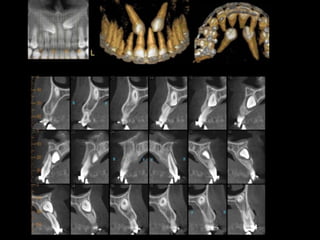

Este documento describe brevemente la historia de la radiografía y los rayos X, y explica que existen diferentes tipos de radiografías y aplicaciones en odontología, incluyendo radiografías intraorales y extraorales. También proporciona ejemplos de actividades para identificar estructuras que aparecen en radiografías dentales de acuerdo a su radioopacidad.